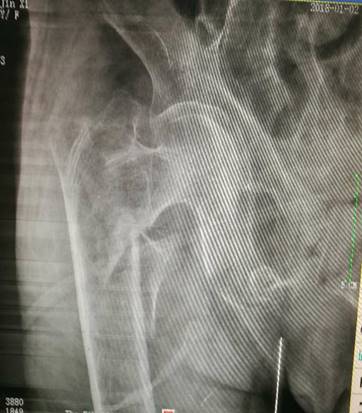

经过相关检查后发现,老太太的右股骨粗隆间粉碎性骨折。刚过百岁大寿的老人,这个粉碎性骨折的消息犹如晴天霹雳,突然降临这个满怀喜庆的家庭。医生午间查房时一家人脸上未曾拭去的泪痕,都在无言诉说着这个家庭的担忧和对老人看护不周的愧疚。

针对百岁老人病情和身体的特殊性,骨科一区医护人员积极准备,及时联系相关科室,在最短的时间内完成术前检查。吕浩然主任在仔细分析术前相关检查,特别是X线片后认为,患者年龄较大,诊断右侧股骨粗隆间粉碎性骨折明确,骨折远端明显移位,如不能及时手术复位,患者1周内死亡风险极高。

术前右股骨正位片